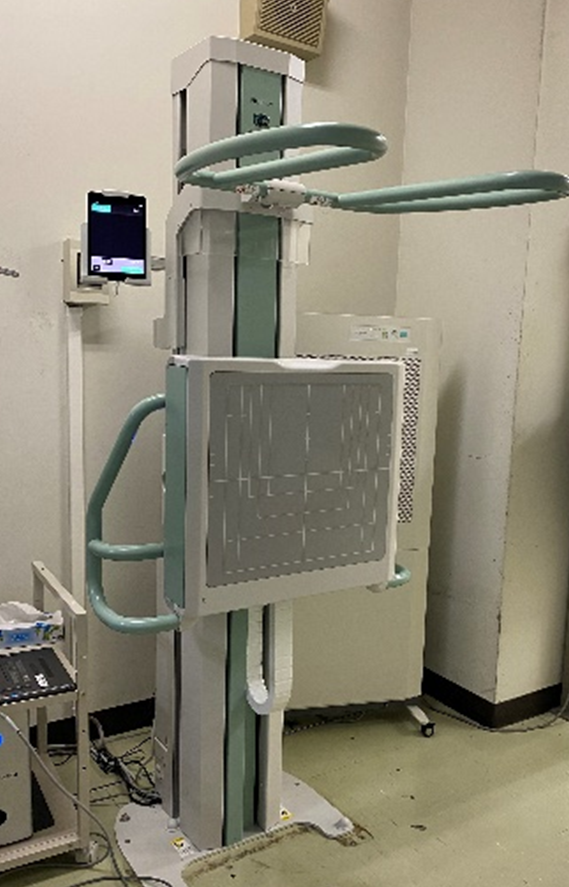

胸部撮影室

FPD:CALNEO Flow G77(FUJIFILM 社製)

レントゲン検査では整形外科の患者数が多く、全脊椎や下肢全長を撮影する検査も増加傾向にあります。当院では DR CALNEO GL(FUJIFILM 社製)を導入しており、より短時間・低線量の長尺撮影が可能となっています。

DR CALNEO GL

撮影室

1番撮影室…主に胸部撮影

2番撮影室…マンモグラフィ撮影

3番撮影室…胸腹部、骨盤部、四肢の撮影

4番撮影室…長尺撮影・頭部・パントモ撮影

5番撮影室…胸腹部、骨盤部、四肢の撮影

7番撮影室…救急撮影